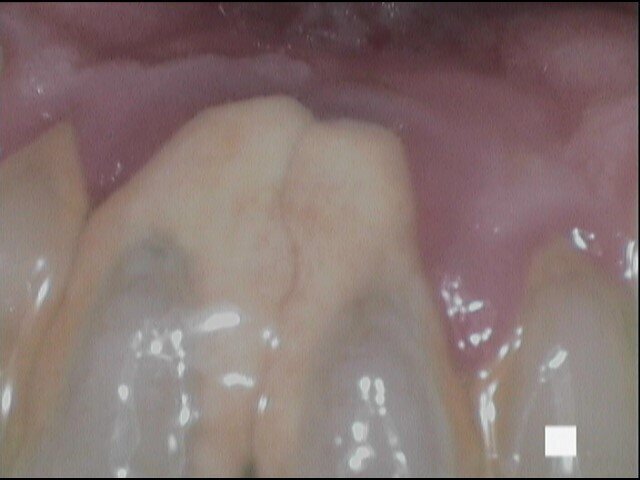

Vengono rilevati gli indici clinici e vengono condivise con il paziente le immagini raccolte con la videocamera intraorale, così da motivarlo di fronte alla presenza di tartaro e infiammazione gengivale e mostrargli le aree critiche. Viene apposto il rilevatore di placca alla fluorescina ed illuminato da una lampada fotopolimeralizzante, che permette di visualizzare la topografia del biofilm batterico (D-BIOTEK-TECNICHE)2, in modo da condividere con il paziente i siti più a rischio del cavo orale (Figg. 1a-2f).